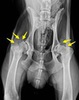

DISPLASIA DE CADERA

¿QUE ES LA DISPLASIA DE CADERA?

La displasia de cadera (DC) es una enfermedad hereditaria del desarrollo de las caderas. Se trata de una patología poligénica (inducida por varios genes, no por uno sólo, por eso es tan difícil de erradicar) y de origen multifactorial (factores como la alimentación, tipo de ejercicio, tipo de terreno, etc, pueden influir en la gravedad de la displasia)

Afecta generalmente a perros de razas grandes ( Terranova, Labrador,